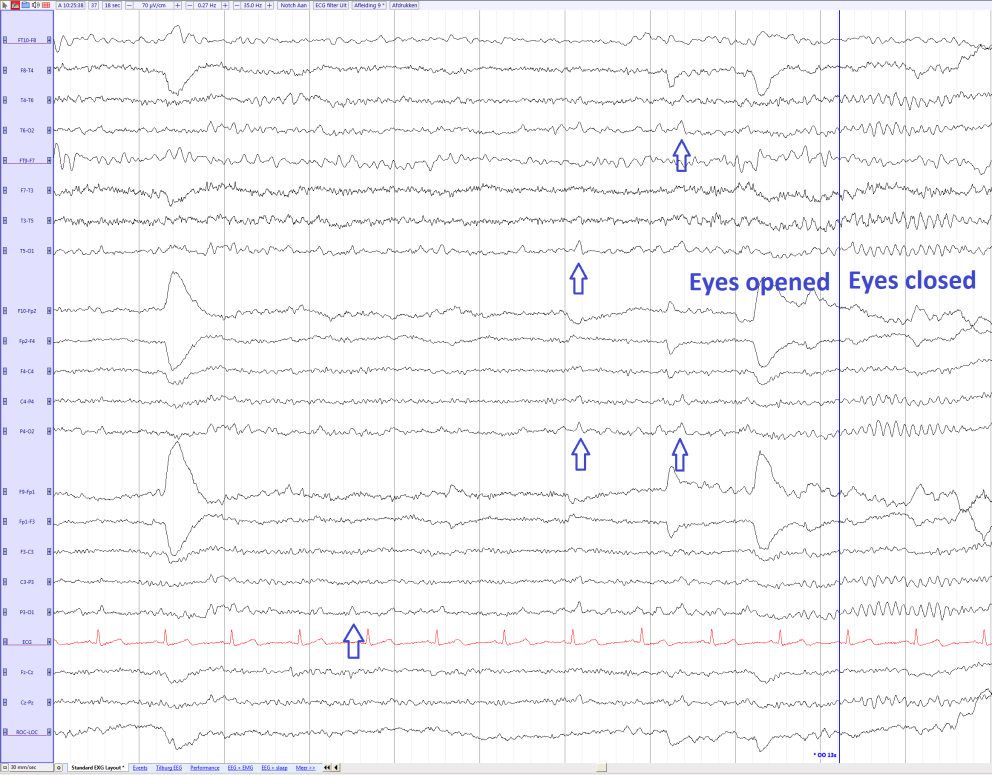

λ波(Lambda Waves)

当患者在视觉上扫描某物时,例如阅读时,λ波会在清醒状态下出现。λ波是双侧对称、轮廓清晰的枕部正波,呈帆状外观,与睡眠后正相尖波(POSTS)非常相似;然而,与POSTS不同的是,λ波伴随着其他清醒的迹象,如眨眼、肌源性伪影等,而不是早期睡眠状态。

极性差异:Lambda波为正相,癫痫样放电多为负相。

Lambda Waves